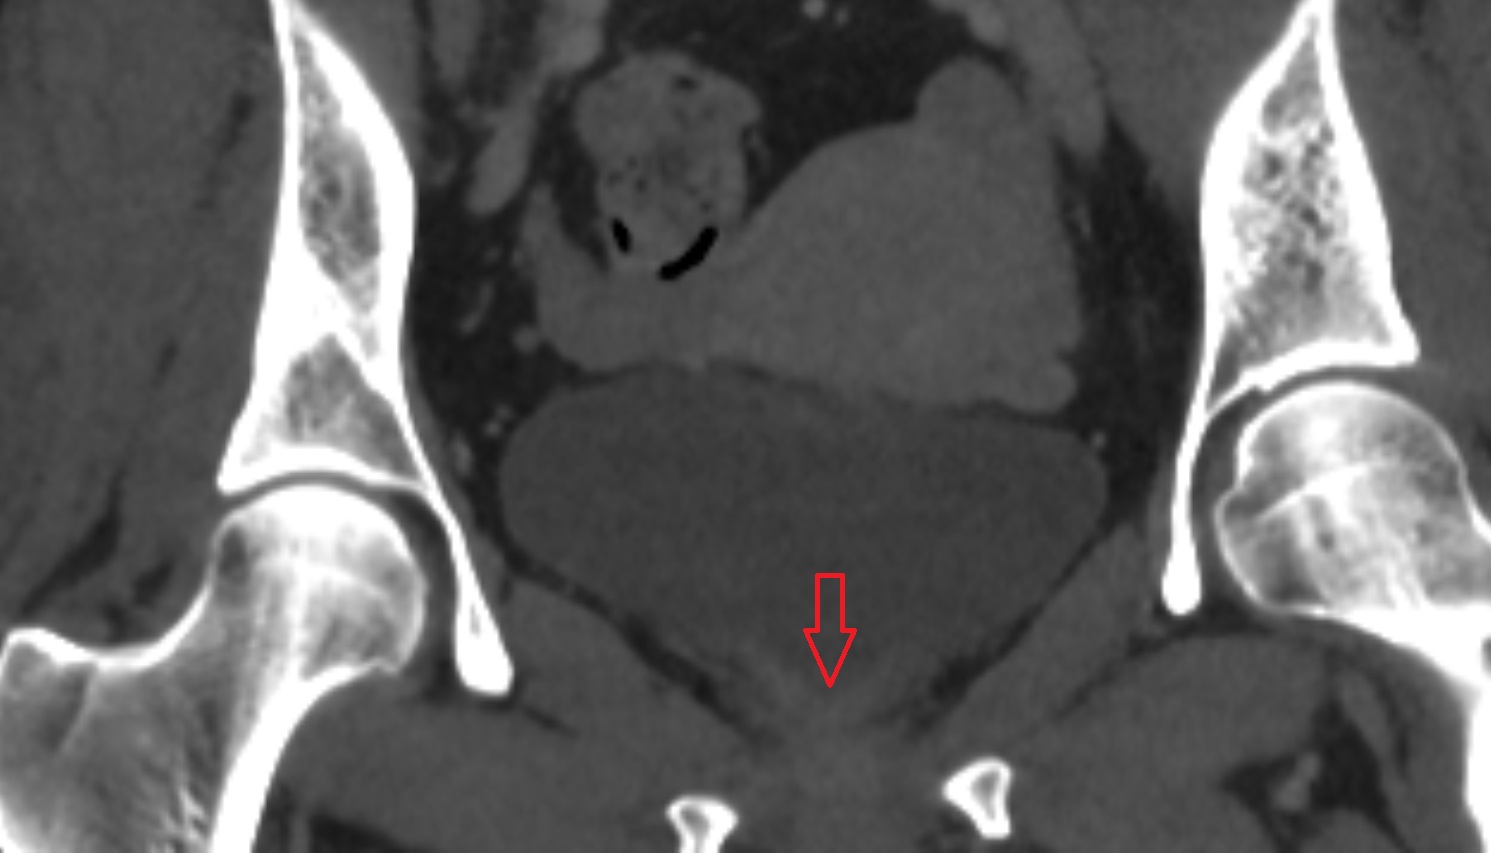

- Uterus

- Body of uterus

- Fundus of uterus

- Cervix of uterus

- Urinary bladder

- Rectum